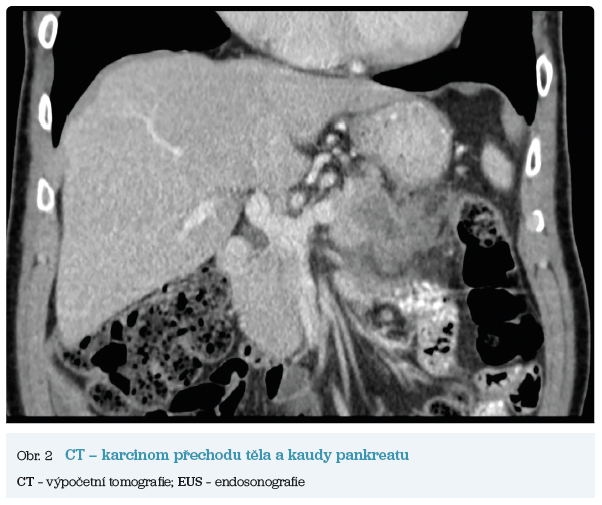

Několik studií se zabývalo AI asistovanou CT detekcí karcinomu pankreatu s AUC 0,79–0,99 %,6–8 tedy přesností porovnatelnou s přesností práce zkušeného radiologa. Stran časné detekce proběhla studie posuzující přesnost AI modelu v detekci karcinomu pankreatu v období 3–36 měsíců před prvními projevy onemocnění. Zařazeno bylo 155 pacientů s karcinomem pankreatu a 265 zdravých kontrol. AI model zde dosáhl AUC 0,98, což výrazně předčilo radiology, kteří při popisování stejných případů dosáhli AUC 0,66.9 Studie využívající DL model pro rozlišení zdravé slinivky od nálezu pankreatických neoplazií, tedy karcinomu pankreatu, intraduktální papilární mucinózní neoplazie (IPMN), serózních a mucinózních cystických neoplazií a solidní pseudopapilární neoplazie, byla prezentována s AUC 0,91, tedy opět odpovídající přesnosti popisu radiologa.10 Pro další vývoj a možné klinické využití bude potřeba přístupu k rozsáhlému archivu CT snímků karcinomu pankreatu, aby se ML modely mohly zdokonalovat. Další studie se věnovaly AI asistované diferenciální diagnostice. Ta bývá u lézí pankreatu velmi obtížná a pokrok v této problematice je tak velmi přínosný. Mezi nejzajímavější patří studie zabývající se rozlišením serózních a mucinózních cystadenomů s AUC 0,932.11 Další studie zkoumala úspěšnost rozlišení karcinomu pankreatu od zbytnění pankreatu při určitých formách chronické pankreatitidy (MFP – mass forming pancreatitis) s AUC 0,866.12 V další studii byla AI využita k rozlišení fokální autoimunitní pankreatitidy od karcinomu pankreatu s AUC 0,97.13 V rámci MR proběhlo několik studií, které se zaměřily na AI asistované zachycení a klasifikaci pankreatického karcinomu či IPMN. Studie klasifikující IPMN pomocí konvoluční neuronové sítě (CNN – convolutional neural network) byla schopna rozlišit dysplazii vysokého stupně od přítomnosti karcinomu se senzitivitou 76 %, specificitou 78 % a AUC 0,78.14 Další studie porovnávala AI modely CT a MR v predikci maligního IPMN. Výsledky ukázaly, že MR model s AUC 0,94 byl přesnější než CT model s AUC 0,864.15 S využitím PET/CT byl prozkoumán AI model rozlišující od sebe akutní pankreatitidu a karcinom pankreatu s AUC 0,9668.16 Výsledky AI v oblastech zobrazovacích metod jsou tak slibné. Dosahují minimálně přesnosti srovnatelné s radiologem a zejména v problematice časných karcinomů pankreatu člověka svojí přesností převyšují (obr. 1–5).

EUS umožňuje přesné vyšetření pankreatu. Lze také identifikovat a vyšetřit regionální lymfatické uzliny a vztah pankreatických lézí k okolním cévním strukturám. EUS může také sloužit jako navigace k odběru bioptického materiálu k cytologickému a histologickému vyšetření.21 AI je zde využívána k potvrzení malignity v IPMN. Kuwahara a kol. dosáhli s využitím 3 970 snímků a CNN algoritmu velké úspěšnosti v diferenciaci benigní a maligní IPMN s AUC 0,98.22 Řada studií se již zabývala AI asistovaným rozlišením chronické pankreatitidy a karcinomu pankreatu s AUC 0,940–0,986.23,24 Velká studie obsahující 1 174 461 snímků z celkem 583 případů hodnotící rozlišení autoimunitní pankreatitidy, karcinomu pankreatu, chronické pankreatitidy a normálního pankreatu dosáhla pro karcinom pankreatu AUC 0,97625 (obr. 6–9).